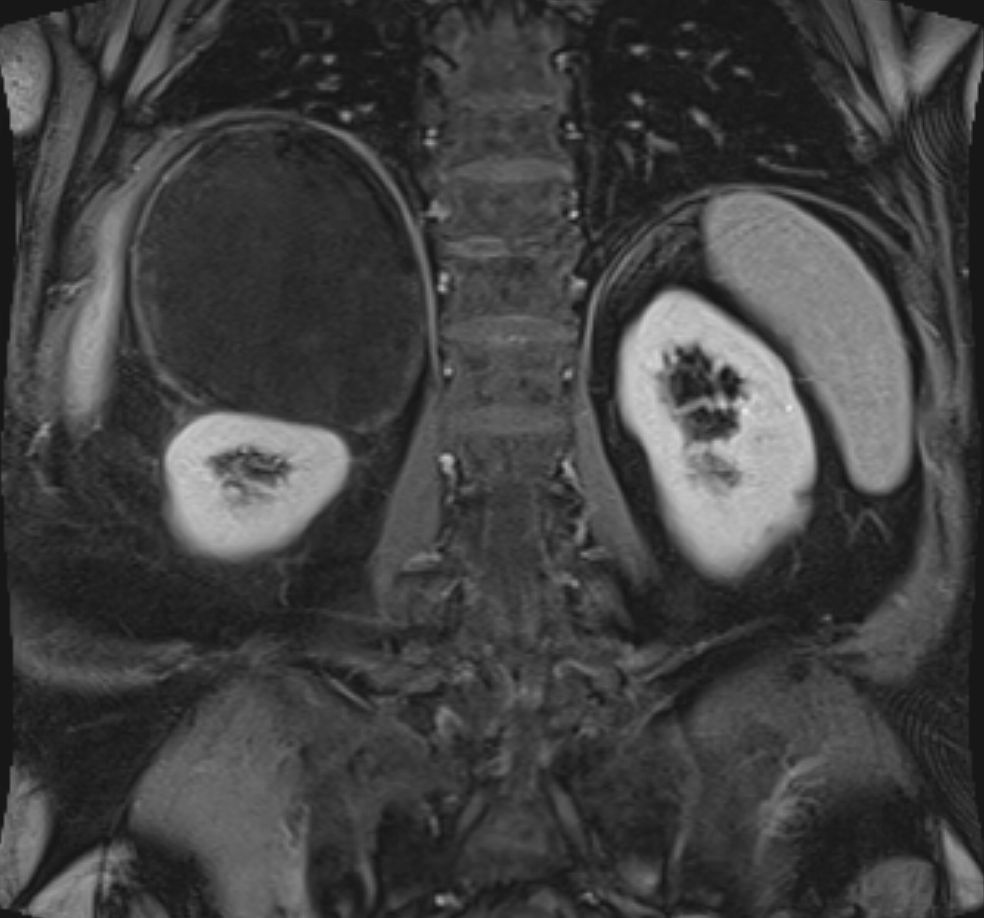

79-jähriger berenteter, adipöser Fleischer mit respiratorischer Insuffizienz. Urothel-Ca vor 15 Jahren. Jetzt kleines Bronchial-Karzinom. Beim Tumorstaging wurde ein großer NN-Tumor rechts entdeckt. | |||